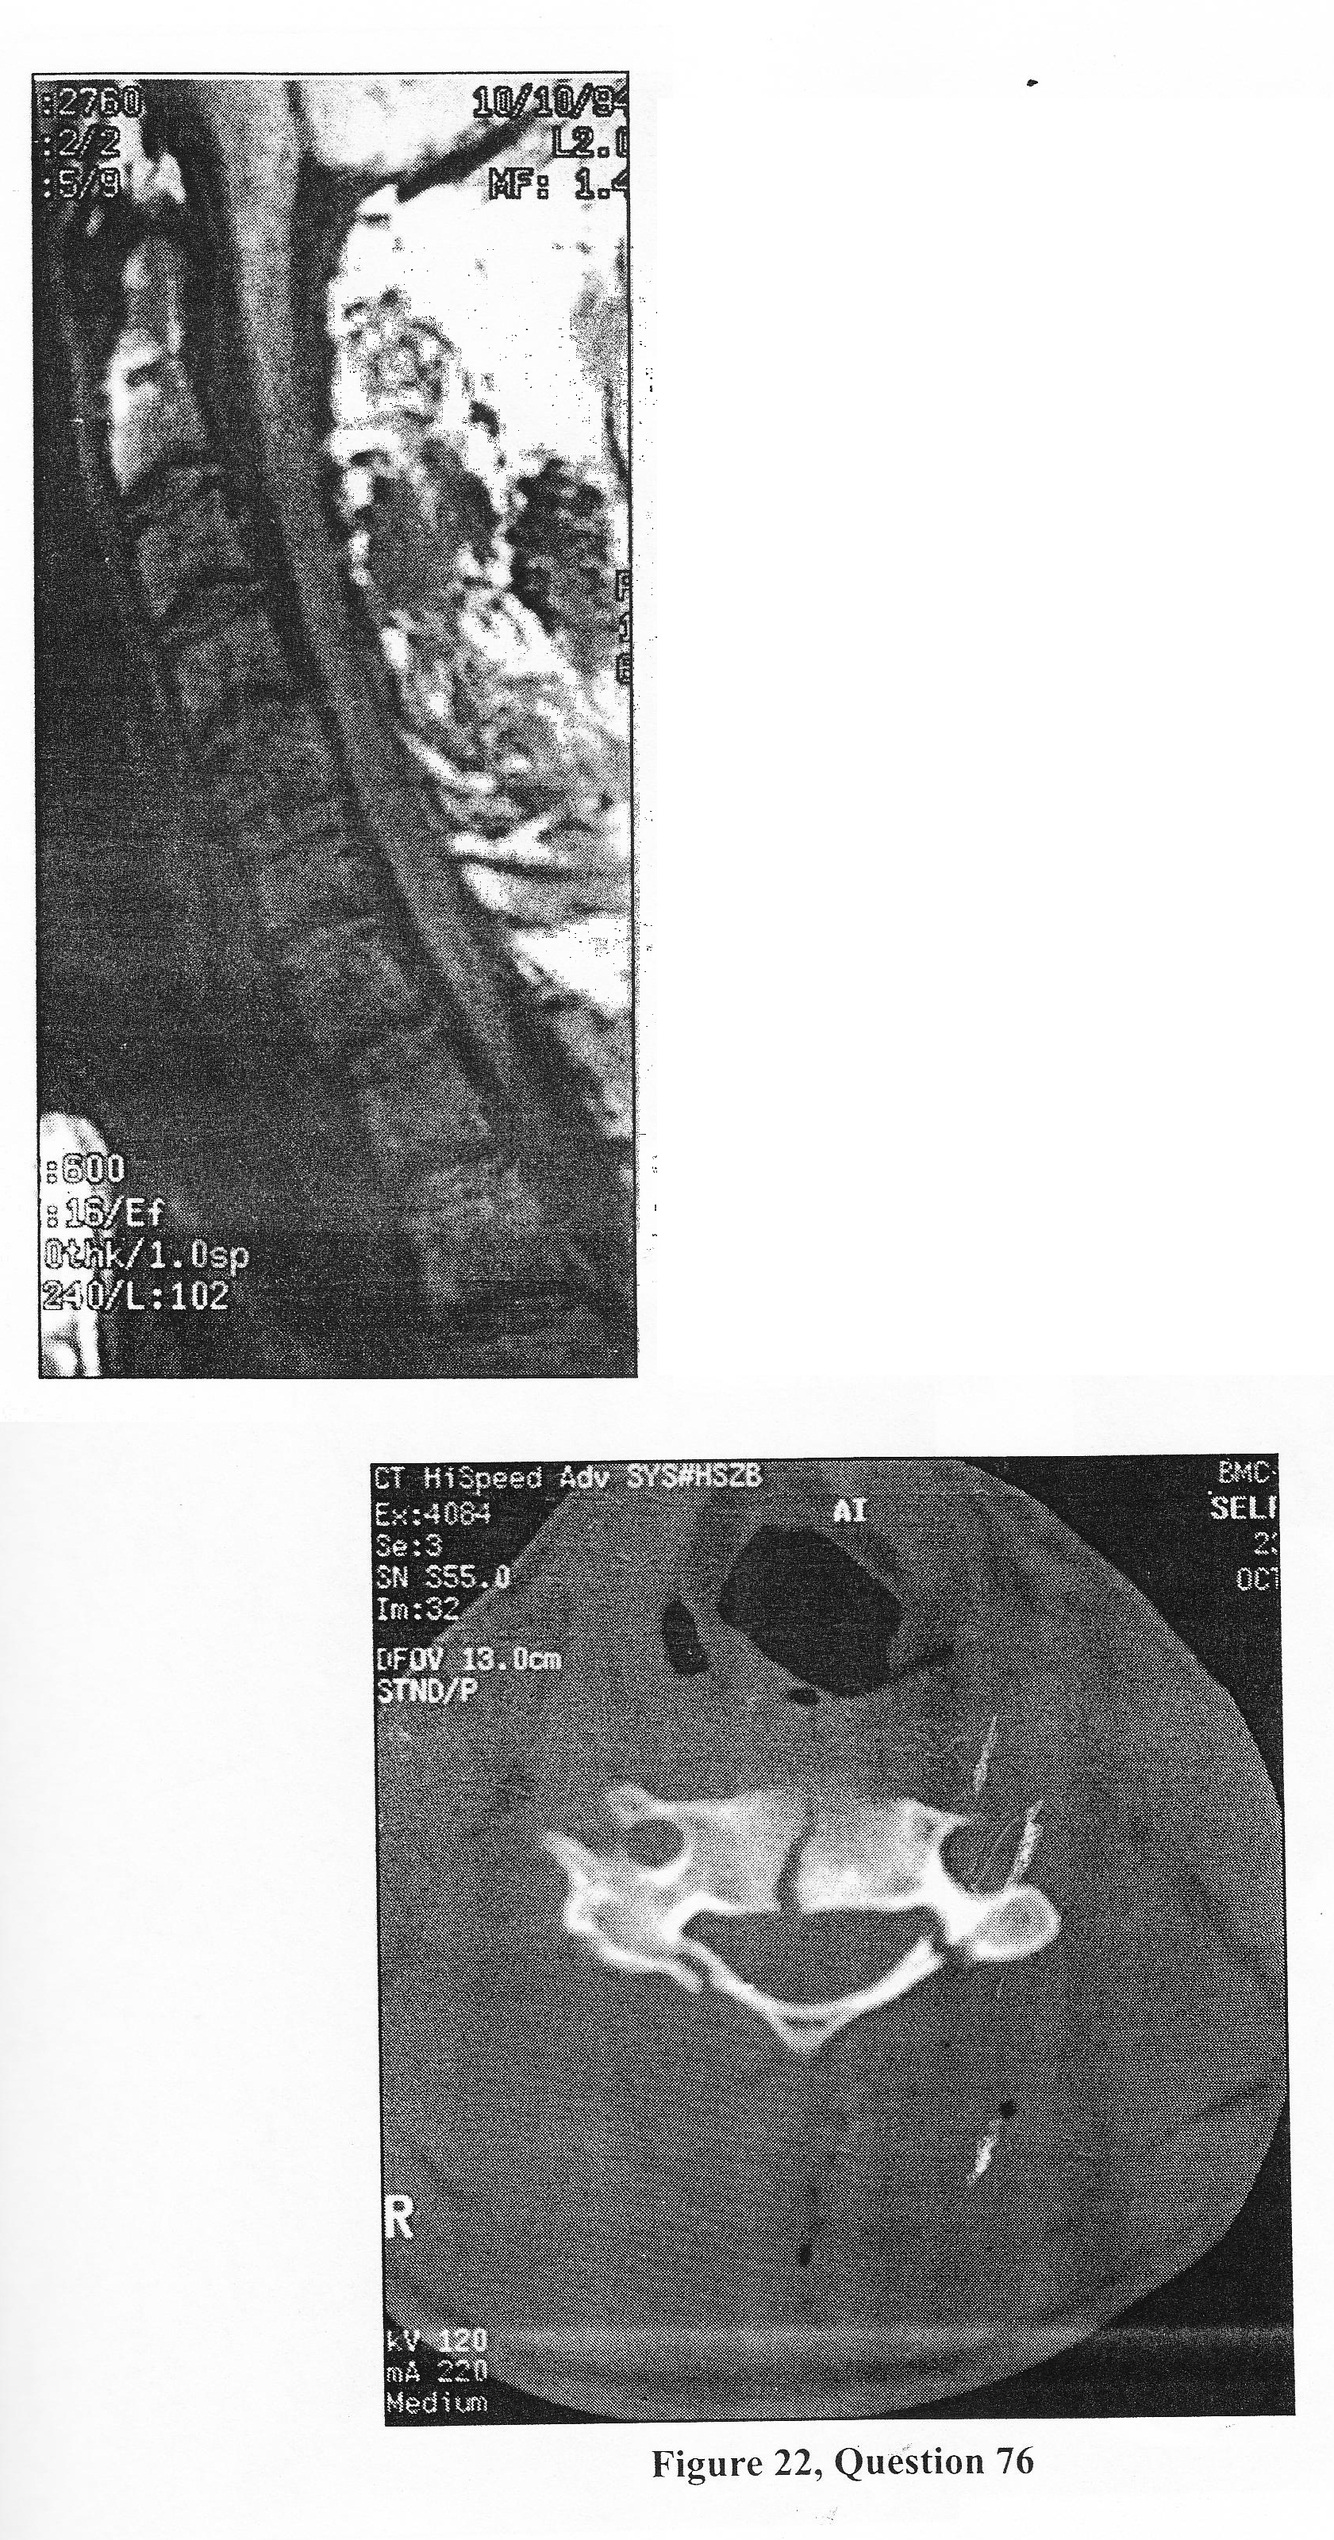

A 50-years-old male with known polyarthritis was taking 10 mg of prednisone daily for several years when he begin complain of disabling bilateral leg numbness, burning dysesthesias, and pain while walking. He reports that he h as fallen several times due to weakness in his legs. Physical exam revealed positive straight-leg raising at 60 degrees bilaterally. Pinprick was diminished in the S1 distribution bilaterally. Sagittal and axial MR images through the lumbar spine are shown in figure 17 and 18.

C. epidural lipomatosis

D. Lumbar laminectomy and fat debulking